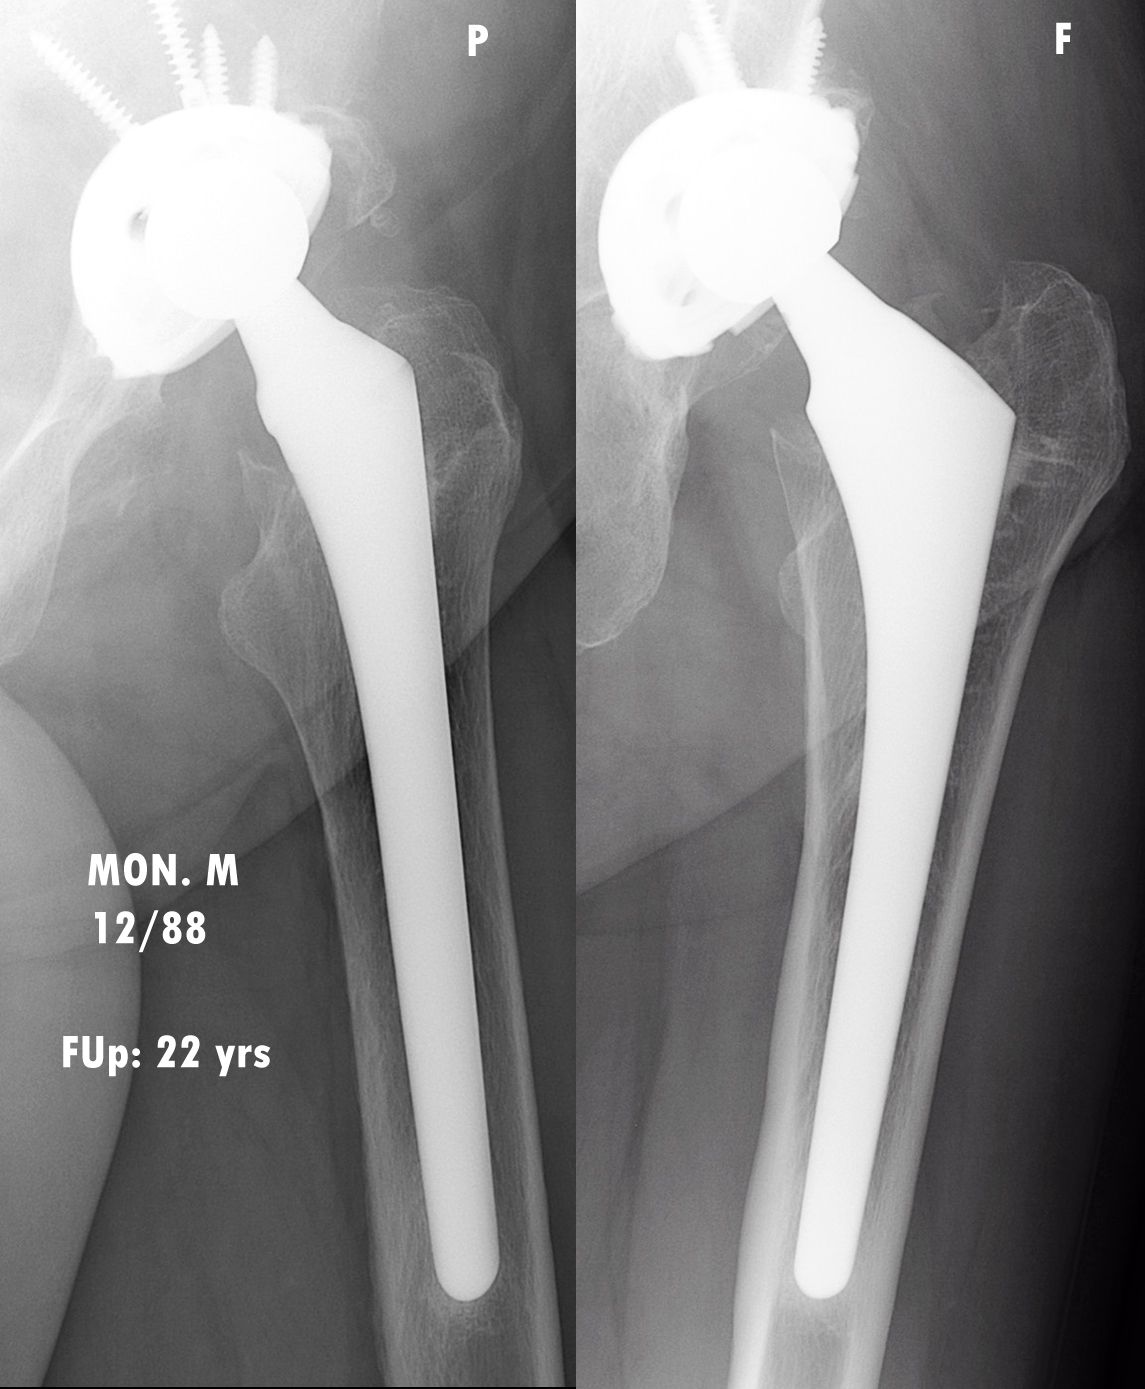

The minimum follow-up for the study was 20 years, and it encompasses two families of proximally HA-coated stems, first the Omnifit HA, which was used between 1987 and 2000, followed by the ABG II from 2001 onwards. Both models are made from titanium alloy coated with a thin layer of hydroxyapatite (60 microns) on their proximal third to provide a ‘metaphyseal-engaging’ design. As counterpart to the stem, the acetabular component used until 2007 was the Arc 2F HA-coated screwed cup comprising a standard PE insert until 1998 then a ceramic-on-ceramic cup in 1999 and 2000, replaced with a highly crosslinked PE insert in 2001.

Overall, these proximally HA-coated stems demonstrated excellent osteoapposition, optimal radiological fixation with bone growth in all cases, and no deterioration in outcomes even after 20 years. (Figs. 3, 4 & 5).

Whatever the timescale, these proximally HA-coated stems produced excellent results, even in this ‘high-risk’ population, and the outcomes were long-lasting, with no deterioration over the years, even in the very long-term after 2–3 decades. These excellent clinical outcomes are corroborated by the radiological study, which confirms bone growth in all cases for the two types of stem studied, confirming previous publications [10] and without any deterioration over time.